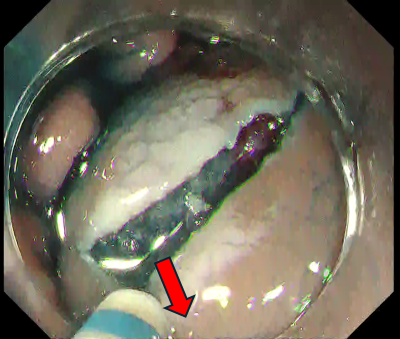

Fig. 2 shows the initial phases of case 1, illustrating how a properly executed local injection allows wide spreading with a single incision and facilitates subsequent introduction into the submucosal layer.

Fig. 1 Ideal local injection

Fig. 2